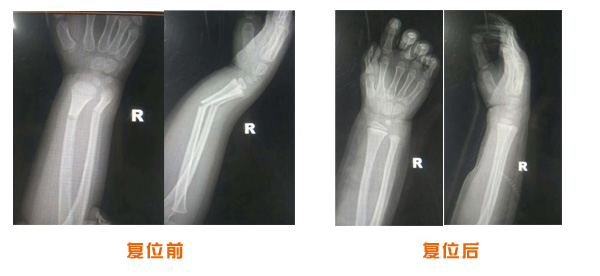

肘關(guān)節(jié)脫位骨折治療前后對比

尺橈骨骨折治療前后